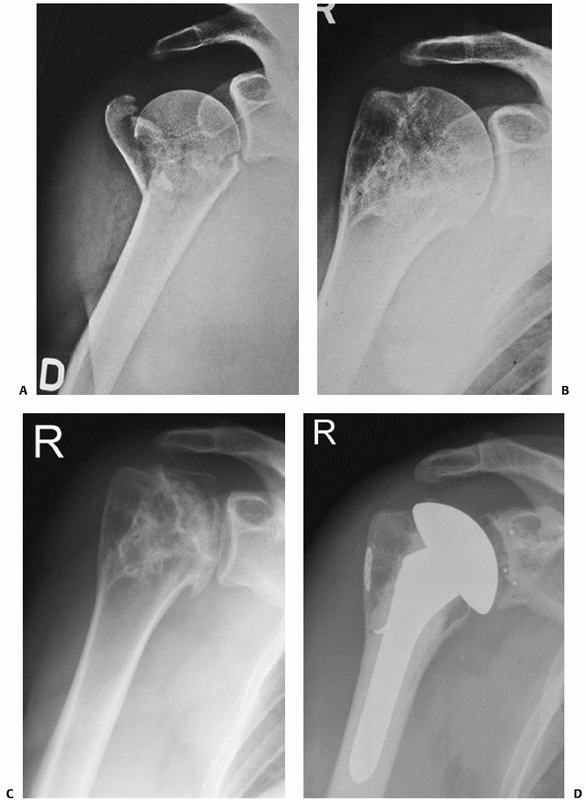

![]() |

FIGURE 35-9 A,B.

Undisplaced and stable fracture configurations are best treated nonoperatively in most elderly patients, as shown in these two examples. |

FIGURE 35-11 (continued) Greater tuberosity fractures vary widely in their size, ranging from larger fragments (D) to smaller avulsion-type injuries (E).

These may displace in the same manner as a rotator cuff tear, with retraction of the tendon leading to progressive displacement of the bone fragment (arrow) (F). Untreated, this may lead to a rotator cuff-deficient shoulder with a high-riding humeral head and rotator cuff arthropathy (G). |